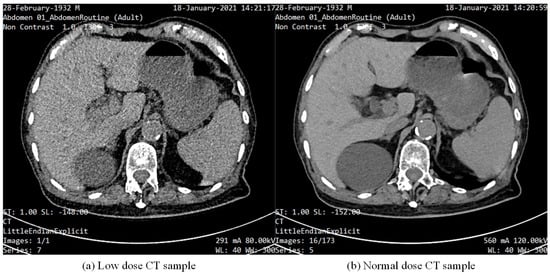

The AAPM dataset is mainly derived from the data of the 2016 Low-Dose CT Grand Challenge of the American Association of Physicists in Medicine. These data are provided by several top hospitals and research institutions and contain CT scan images of the human body, covering different parts such as the chest and abdomen. The samples in the AAPM-Mayo dataset are shown in Figure 6, where (a) is an LDCT abdominal image and (b) is an NDCT abdominal image.

Figure 6.

Samples from the AAPM−Mayo dataset, where (a) is an LDCT abdominal image and (b) is an NDCT abdominal image.

The CT images in the AAPM dataset are stored in the DICOM (Digital Imaging and Communications in Medicine) format. This is a standard format for medical imaging and contains the image itself as well as a large amount of scan-related metadata (such as scan parameters, patient information, etc.). The size of CT images is usually rectangular, with a typical slice size of pixels. The thickness of these slices (i.e., the distance between every two slices) may vary from 0.5 mm to 5 mm, depending on the scan settings and the target area. The AAPM-Mayo dataset contains chest CT images from 10 patients. Each patient’s scan includes both standard dose and quarter dose images. Each patient contains multiple slices of CT images, the exact number of which varies from patient to patient. Typically, each patient’s scan produces several hundred image slices. The number of image slices for a standard dose and quarter dose is the same. Due to the variation in scan data for each patient, the exact total number of images may vary, but it can be estimated that there are several hundred image slices per patient. The AAPM-Mayo Low-Dose CT dataset has approximately 6000 images in total.